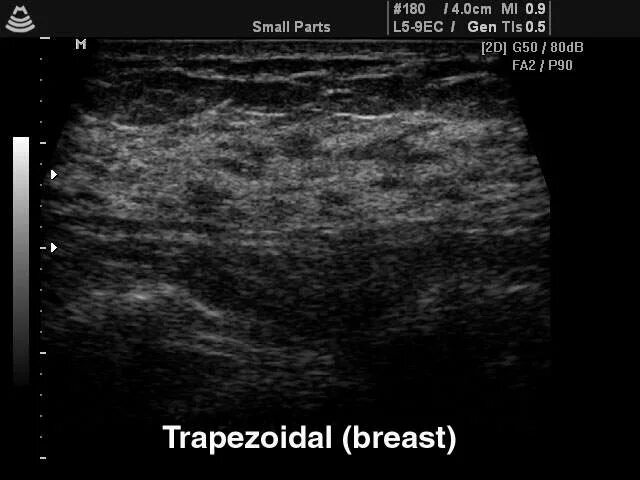

Узи молочных киров